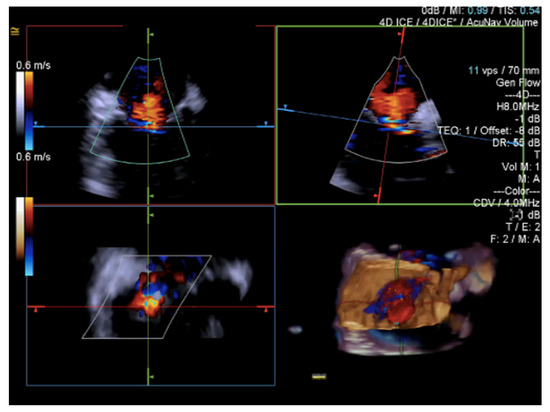

3.2. Intracardiac Echocardiography: Strenghts and Limitations